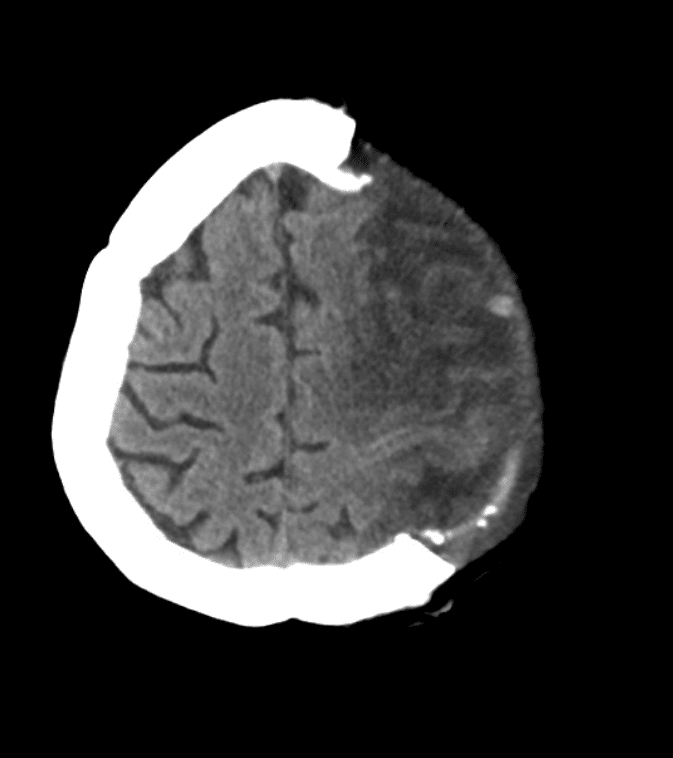

Il giorno successivo viene eseguita una TAC di controllo.

Interpretazione della TAC a 24 ore